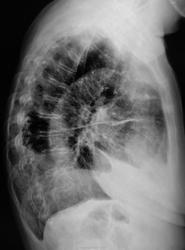

Боковые томограммы.

Добавлены томограммы в боковой проекции.